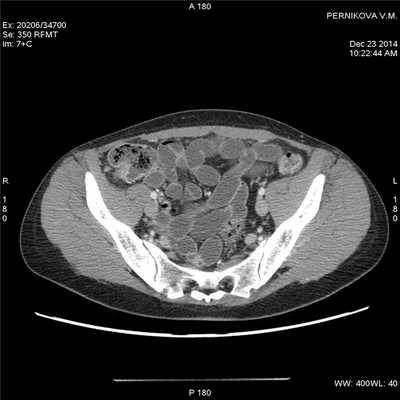

Сакроилеит и анкилозирующий спондилит чаще связаны с язвенным колитом, хотя бывают и при болезни Крона. Свищи при болезни Крона возникают после хирургических вмешательств или спонтанно. В частности, тонкокишечно-кожный свищ чаще встречают в области послеоперационного рубца. Внутренний свищ включает любые комбинации тонкой и толстой кишки друг с другом, а также мочевым пузырем и влагалищем. Перианальный свищ рассмотрен в отдельной статье на сайте. Несмотря на то что в некоторых случаях бывает достаточно лечения азатиоприном или инфликсимабом, многие свищи требуют хирургического вмешательства.

Двусторонний сакроилеит при болезни Крона. Позвоночный столб без изменений, признаков анкилозирующего спондилита нет. Рентгенограмма таза.